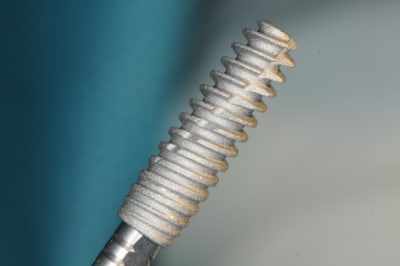

10 l'AXIOM PX

(diamètre 4; dans le cas précédent c'était un diamètre 3.4 on voit qu'ici il y a une réduction du diamètre du col de l'implant contrairement au 3.4 pour eviter de fragiliser l'implant)